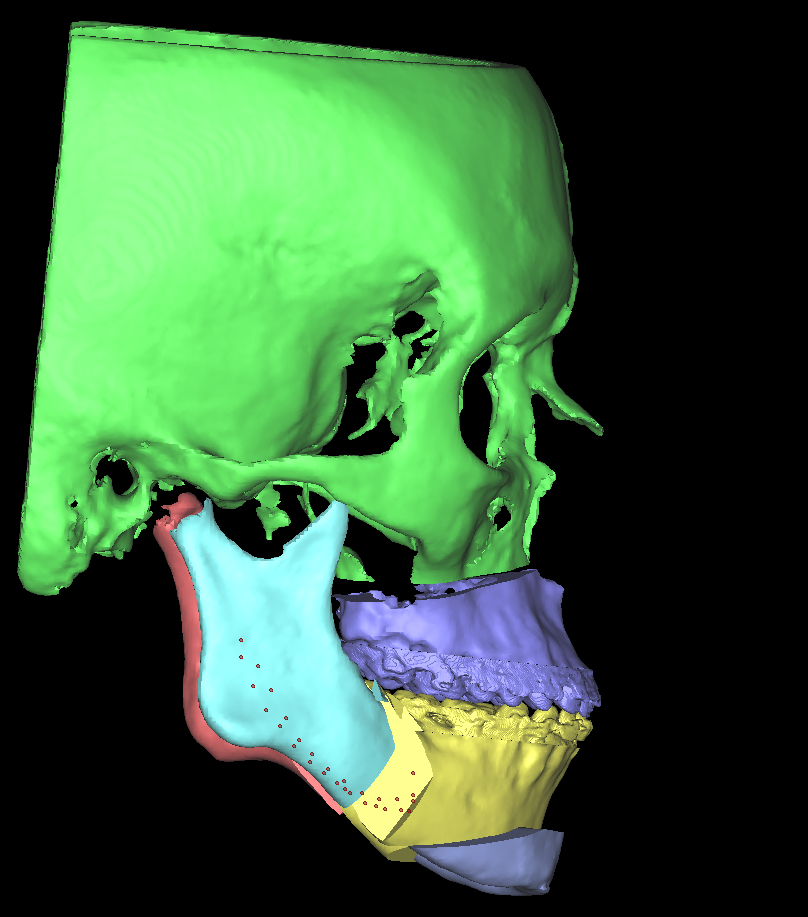

Als de orthodontische voorbereiding voor de operatie ver gevorderd is, wordt de kaakoperatie door de kaakchirurgen digitaal gepland in 3D.

Met een prachtig digitaal planningsprogramma in samenwerking met het UMCG, wordt bepaald wat het mooiste resultaat geeft. Hieronder geven we voorbeelden van hoe zo’n planning er uit kan zien. In dit voorbeeld wordt de bovenkaak verplaatst, de onderkaak en de kin. Vaak kan de operatie ook beperkt worden tot alleen een onderkaak of alleen een bovenkaak. Het is maar net wat per specifiek geval de beste oplossing is.

en het effect daarvan op de ‘weke delen’ zoals lippen en kin en profiel.

Nu kan dee kaakchirurg goed voorbereid de operatie plannen.